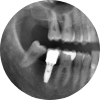

어금니 임플란트

씹는 힘을 지키는 치료, 어금니 임플란트 미르가 완성합니다.

어금니는 강한 저작력이 있어야 하는 치아로, 음식물을 잘게 부수고 소화를 돕는 중요한 역할을 합니다.

따라서 어금니를 상실했을 경우, 가능한 빠른 시기에 기능을 회복하는 것이 매우 중요합니다.

수원미르치과는 어금니 상실 시, 빠른 기능 회복은 물론 안정적인 교합까지 고려한 정밀한 임플란트 치료를 제공합니다.

보이지 않는 부분까지 완성도 있게, 기능 중심의 치료 철학을 지켜갑니다.